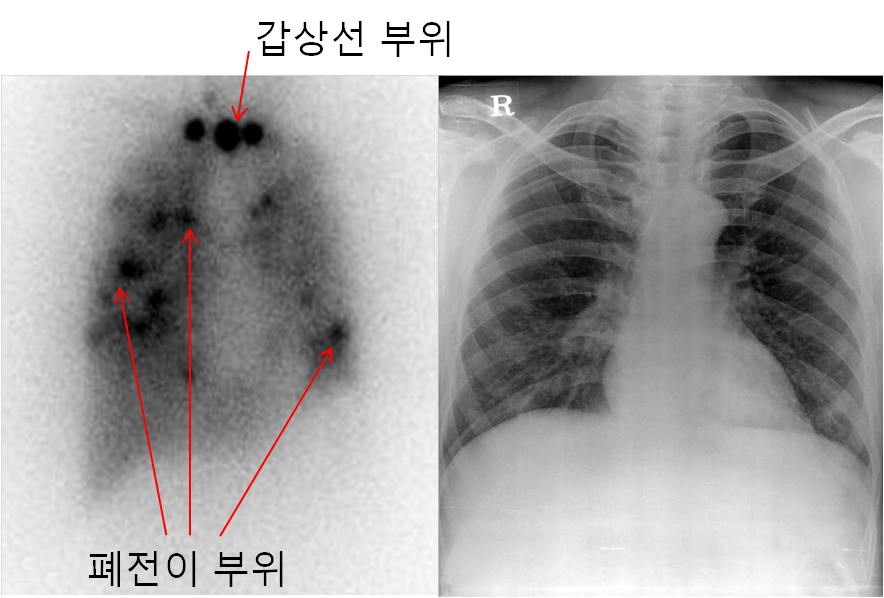

방사선 요오드 전신 스캔은 특히 폐전이의 발견에 높은 민감도를 나타냅니다. 갑상선 암은 속립성 폐전이(조그만 병변들이 퍼져서 나타남)경향이 있어 흉부 X-ray 검사에선 관찰되지 않는 경우도 많으며, 심지어 흉부 CT에서도 병소가 관찰되지 않고 방사선 요오드 전신스캔에서 전반적으로 높은 폐섭취를 보이는 경우도 있습니다. 이런 방사선 요오드 전신스캔에서만 관찰되는 전이의 경우 방사선요오드 치료에 반응이 좋으며,CT등 다른 영상에서 관찰 되는 경우보다 좋은 예후를 보인다고 알려져 있습니다.

아래의 사진은 폐에 전반적으로 방사선 요오드에서 방출되는 방사선을 측정한 것으로 동그랗게 보이는 까만 점이 방사선을 방출하고 있는 곳입니다. 즉, 갑상선 조직들이 있어서 섭취된 방사선 요오드를 흡수했고 그 방사선 요오드 방사선이 방출되고 그러면 이렇게 까만 점이 보이는 것입니다. 그러나 이런 것만 가지고 판독을 할 수는 없는 것이구요 환자분의 전반적인 상태등을 고려하면서 판독해야 합니다. 그래서 판독은 핵의학과 전문 선생님께서 하셔야 합니다.